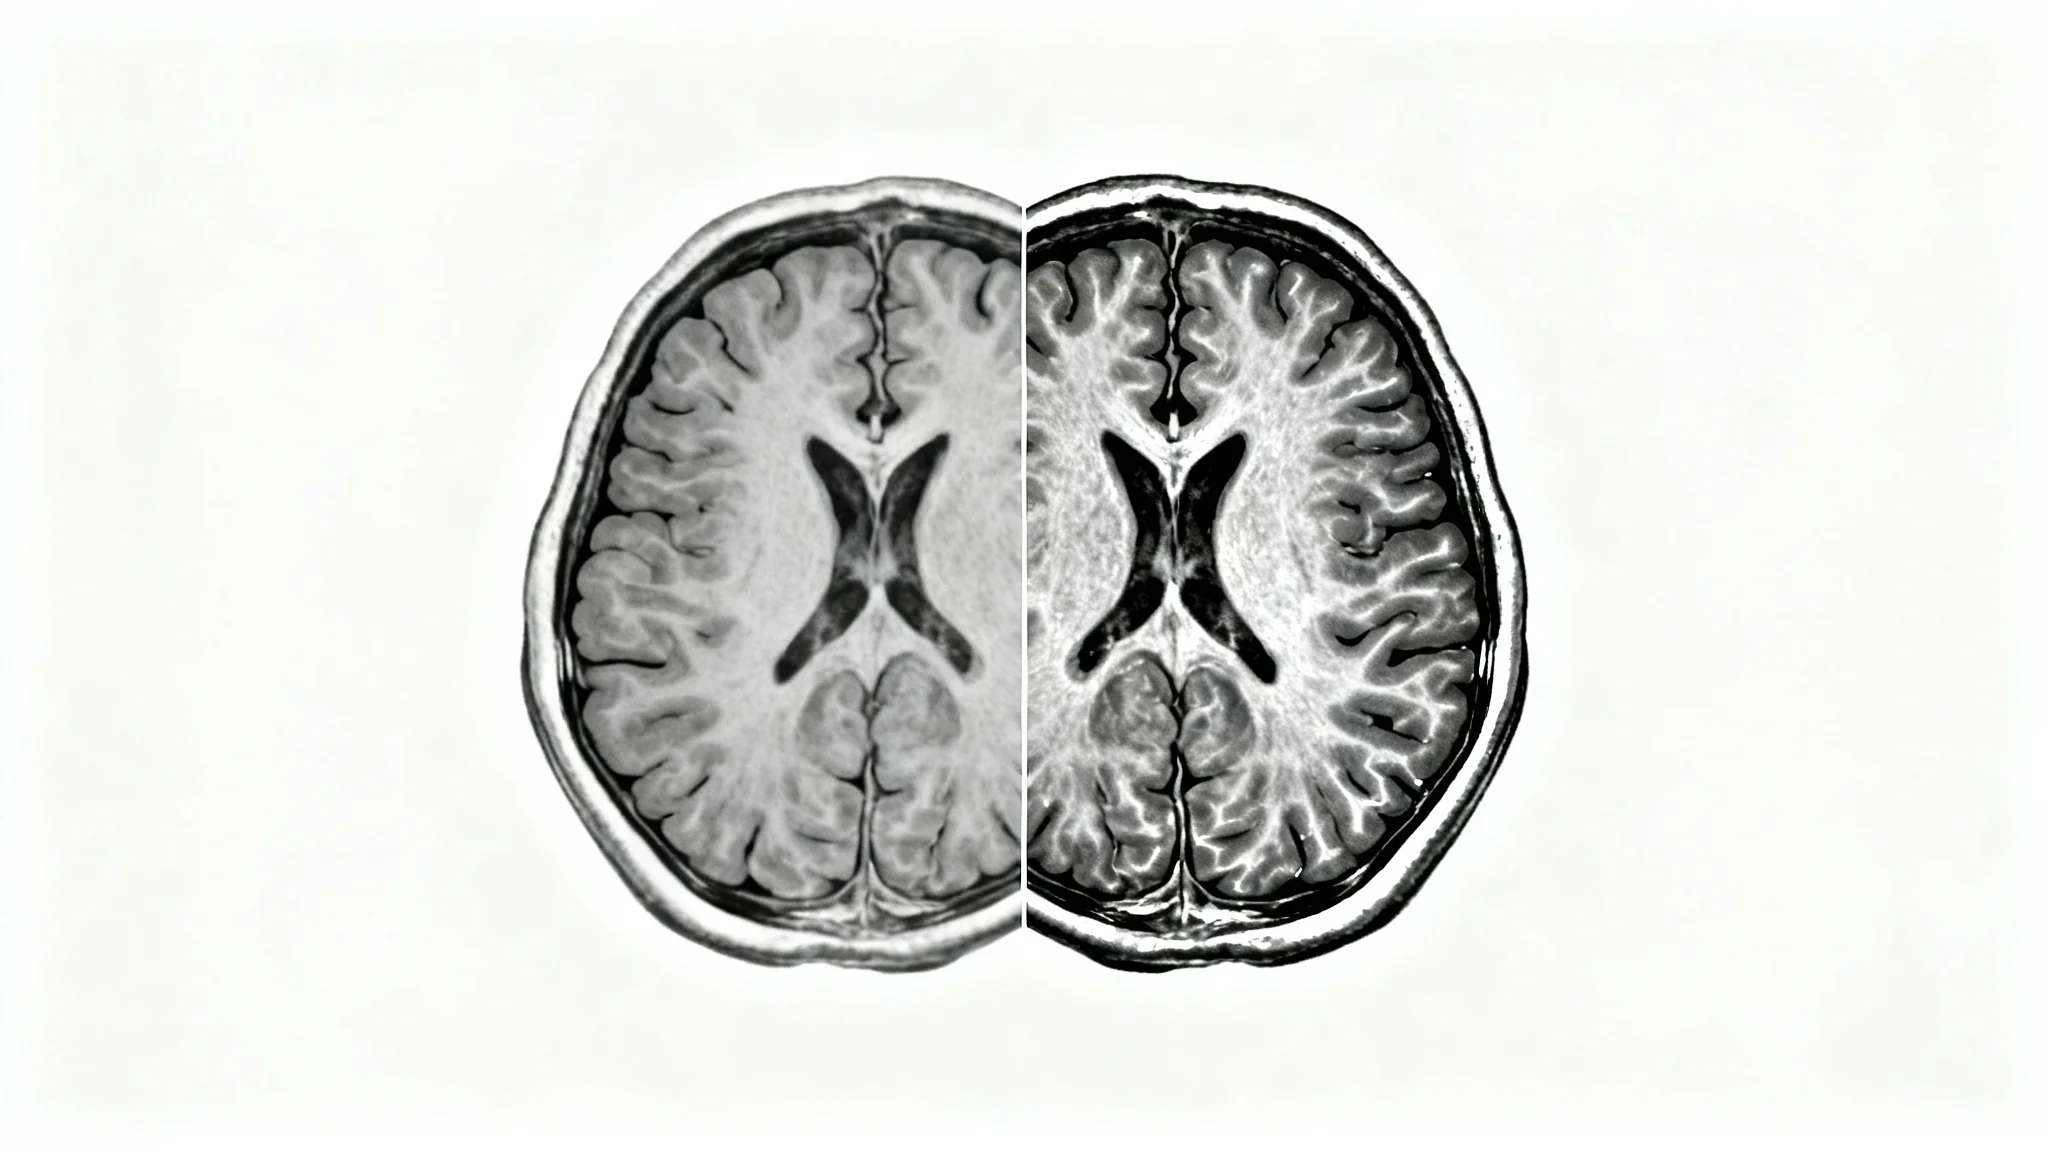

A side-by-side comparison of a human brain MRI scan. The left image is a standard grayscale scan, while the right image shows the same scan with contrast enhancement, making a tumor brightly visible and sharply defined.

Remove the variability that comes with manual adjustments. Our AI applies a consistent enhancement protocol every time, ensuring that results are standardized and reproducible. This is especially valuable for longitudinal studies where tracking disease progression requires reliable, comparable images over time. The algorithm is trained to recognize and enhance pathological features with precision, providing a dependable level of quality that helps standardize image interpretation across different scans and patients.